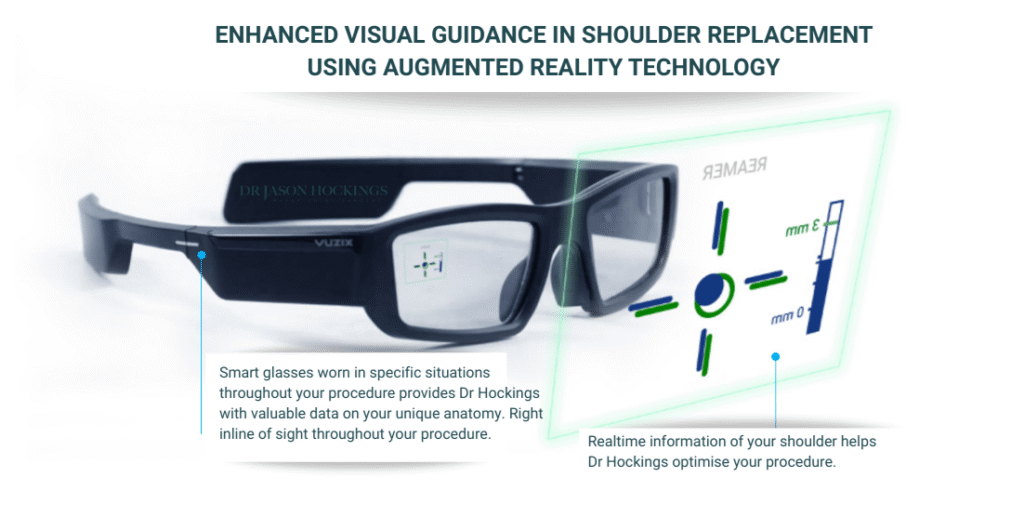

Dr Hockings performs reverse shoulder procedures using either a deltopectoral or superior approach, depending on your anatomy and clinical needs. During surgery, he also incorporates an augmented reality surgical platform called NextAR that uses smart glasses to provide live visual feedback based on your personalised anatomical plan.

NextAR Shoulder enhances accuracy by overlaying live metrics such as:

- Glenoid inclination and version

- Baseplate positioning and screw trajectory

- Offset and depth measurements in real time

A recent study showed exceptional alignment accuracy, with deviations from the pre-op plan as low as ~0.6° in angle and less than 1 mm in position, demonstrating superior execution of the surgical plan.